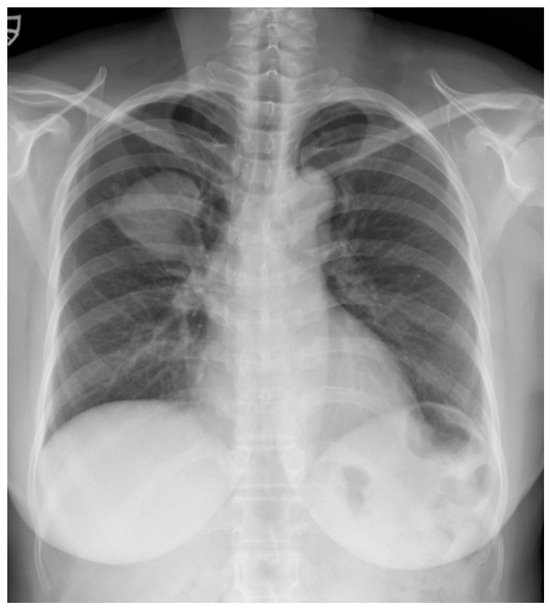

A 52-year-old woman was admitted to our hospital with a three-month history of cough and sputum, along with a one-month history of hemoptysis. Her medical history was unremarkable, and she was a nonsmoker. The laboratory results were within normal limits. Chest radiography revealed a well-defined mass-like opacity with a partially lobulated lateral edge in the right upper zone (Figure 1). Unenhanced CT showed a homogeneous hypodense mass (Hounsfield Unit: 20) measuring approximately 56 × 44 × 42 mm in diameter, with well-defined, mostly smooth, but partially lobulated margins in the right upper lobe (Figure 2a). The mass effect caused splaying of the anterior and posterior segmental bronchi, unlike bronchial obstruction typically observed in lung cancer (Figure 2b). Contrast-enhanced CT (CECT) revealed a predominantly poorly enhancing mass resembling a cystic lesion with a small but strong nodular or curvilinear peripheral enhancement (Figure 3). No mediastinal adenopathy was observed.

Figure 2.

(a) Unenhanced chest CT showed a homogeneous hypodense mass (5.6 cm in diameter) in the right upper lobe (white arrow). The mass had a well-defined shape with a primarily smooth, but partially beak-like lobulated margin. (b) There was splaying of the anterior and posterior segmental bronchi (black arrow) from the mass effect.